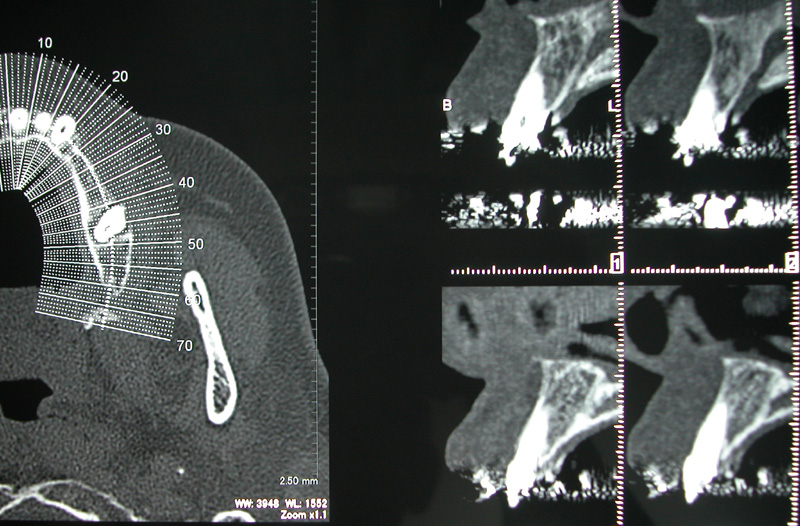

¤³¤Î7·î22Ž¥23Æü¤â¥¤¥ó¥×¥é¥ó¥È¸¦½¤²ñ»²²Ã¤·¤Æ¤¤Þ¤·¤¿¡£

¡¡¤Á¤ç¤Ã¤È

»É·ãŪ¤Ê¼Ì¿¿

¤«¤â¤·¤ì¤Þ¤»¤ó¤¬¡¢ÆÚ¤Î²¼³Ü¤ò»È¤Ã¤Æ¤Î¼Â½¬É÷·Ê¤Ç¤¹¡£

¼ê½ÑÍѤμêÂÞ¤ò¤·¤Æ¤¤¤¿¤Î¤Ç¤¹¤¬¡¢µ¢Â𤷤ƤâÆÚ¹ü¤Î½¤¤¤¬¾Ã¤¨¤º¡¢¡¢¡¢